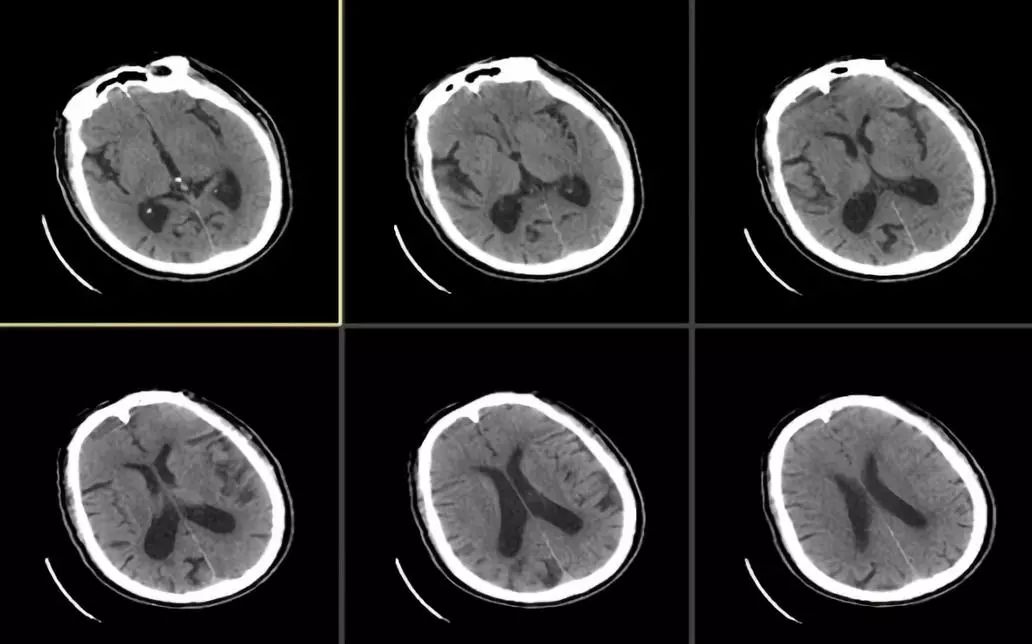

溶栓前头颅平扫CT检查未见明显新发病灶(图1),ASPECTS评分:10分

图1

溶栓后复查头颅CT检查未见出血,但左侧大脑中动脉有高密度征(图2)。

图2